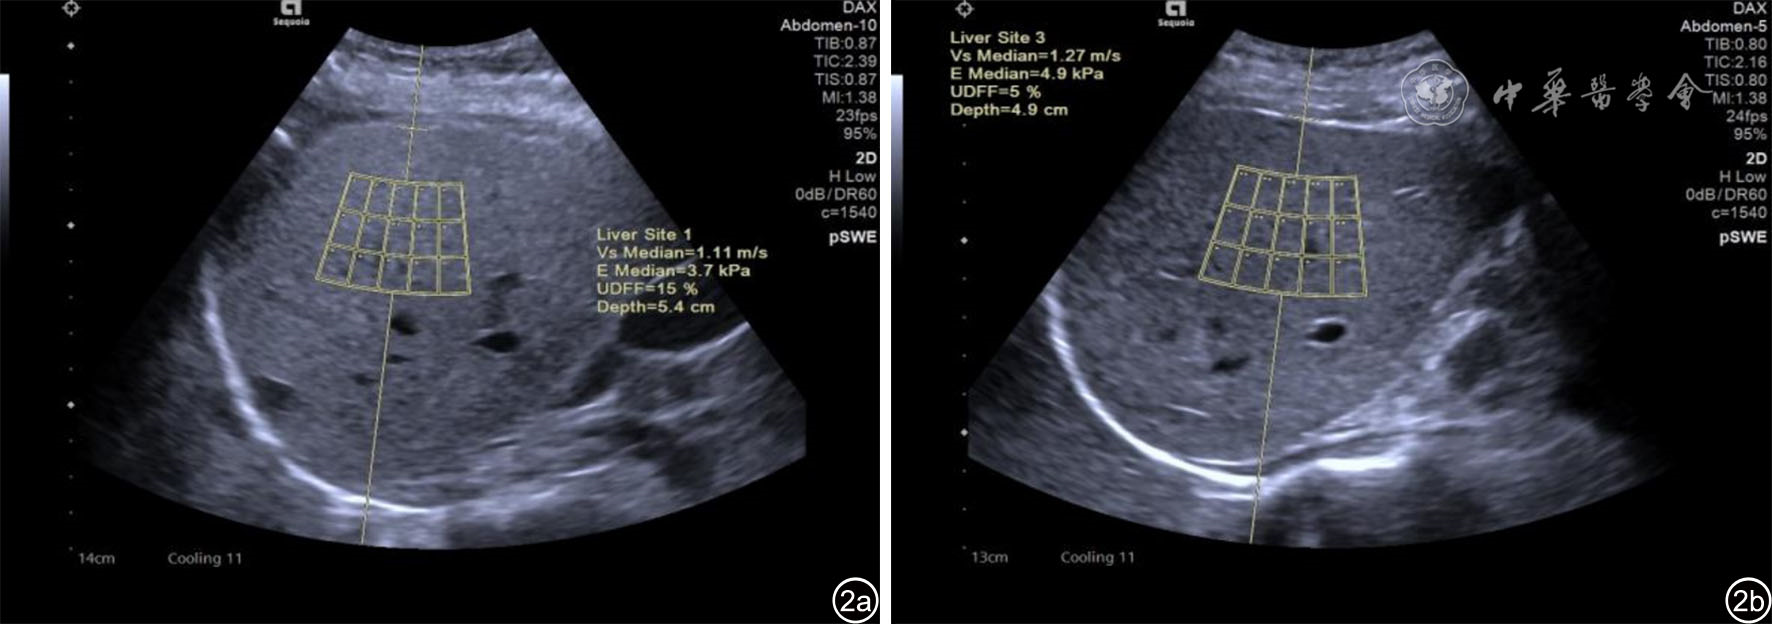

图2 生物声学脂肪分数(UDFF)测量超声图像。使用DAX探头(频率1.0~5.7 MHz),垂直放置于肝右前叶,避开大血管及肋骨阴影区,嘱患者深吸气屏住呼吸5 s,同时开始采集数据,自动获取UDFF值,图a为甘油三酯值为4.0 mmol/L的高甘油三酯血症患者UDFF测量,UDFF=15%;图b为甘油三酯值为1.2 mmol/L的健康受试者UDFF测量,UDFF=5%